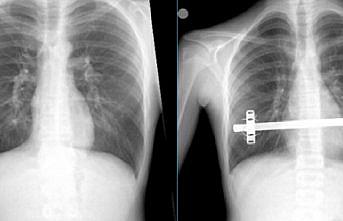

Trabzon'da omurga vidalama ameliyatı geçiren hasta sağlığına kavuştu

Trabzon'da,

Trabzon'da, "kapalı kunduracı göğsü ameliyatı" olan hasta sağlığına kavuştu